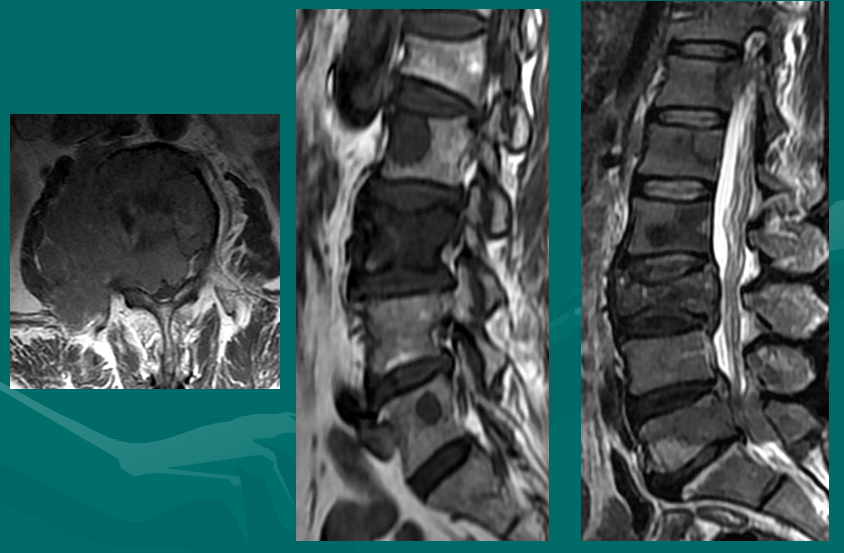

位于椎体之间的椎间盘应是白色的(含水多)。注意黑颜色(脱水的)的L5椎间盘(L5与骶骨之间的椎间盘),这代表了中度到重度的退化性椎间盘病。

后纵韧带(PLL小蓝箭头)在图像中表现为沿着每个椎体及椎间盘后缘垂直向下的黑线。有意思的是,尽管此病人有一个9mm的椎间盘突出(HNP),骨质有一定的翘起,在椎间盘平面以上可见髓核物,但后纵韧带仍然包容着突出的髓核物而没有游离出。这种情况在学术上被称作一个大的包容性椎间盘突出。

硬膜囊(红星)表现为“超白色”结构,填充在椎体后方的中央椎管内。此囊袋内有可自由浮动的由运动神经纤椎及感觉神经纤维共同组成的脊神经根(马尾)。

黄韧带(绿星)位于每个椎骨之间,增强脊柱的稳定性。此结构可变大或增厚,助长年长者易患的中央型椎管狭窄的形成。